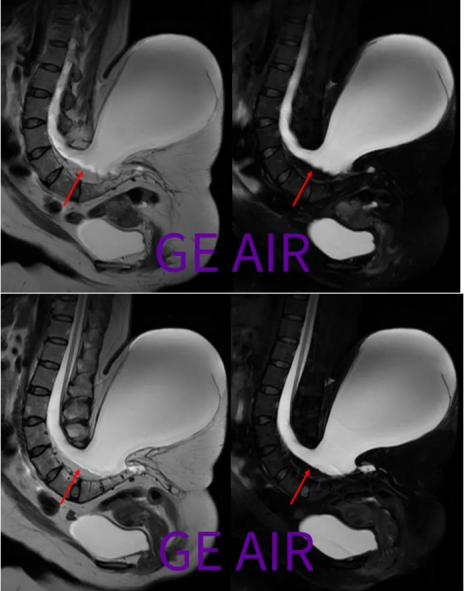

回顾性翻看矢状面T2和T2 fs,由于椎管内脂肪(红箭)和脑脊液交界,化学位移现象很重,所以干扰了囊性包膜的显示。

横断面三维CUBE T2和T1,具有薄层(1mm)高分辨的优势,可以最小化脑脊液流动伪影和化学位移伪影,有助于椎管内和/或邻近椎管区域的病变解剖显示,建议偶遇非常规病例的时候,加扫这么一个序列。 所谓,我为人人,人人为我。